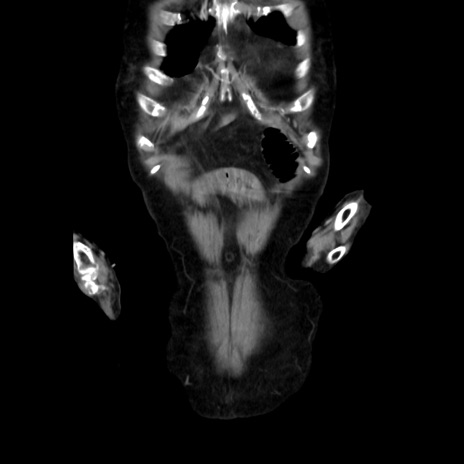

冠状断像

矢状断像